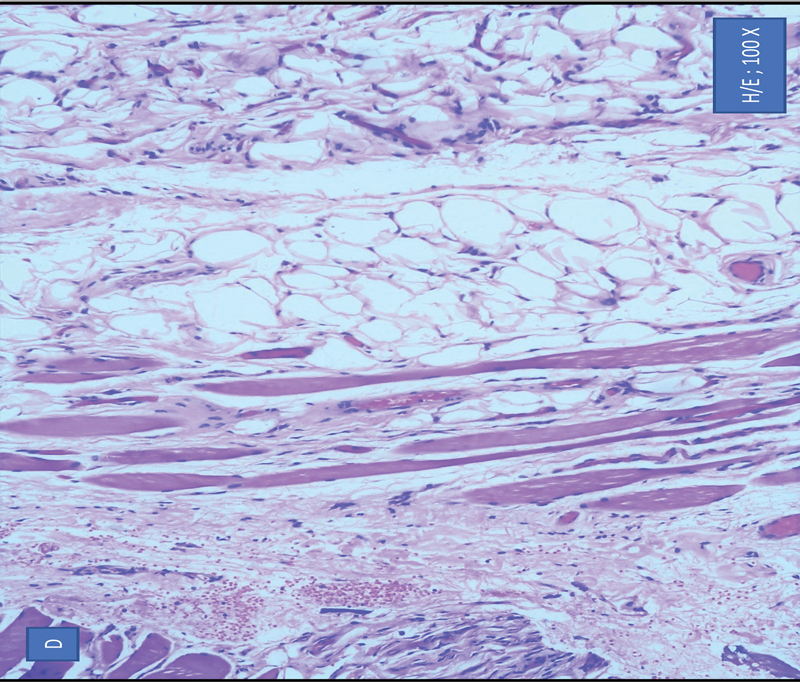

Microscopically, a thin fibrous capsule is seen. The tumor shows lobular architecture separated by variably thick fibrovascular septa.[1] These tumor cells are mature adipocytes with small eccentrically placed nuclei where the nuclei are often compressed ([Fig. 2]) with no notable inflammation, or cellular atypia, lipoblasts, or features of malignancy. Thus, final diagnosis was histopathologically confirmed as lipoma.

| Figure 2: Microscopically the sections showing sheets and lobules of benign adipocytes separated by variably thick fibrovascular septa. Focally, the adipocytes are seen to infiltrate around skeletal muscle tissue.